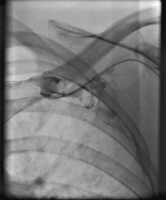

Präinterventionelle Angiographie

Abbildung 4: Verschluss Vena subclavia und axillaris in der präinterventionellen Angiographie